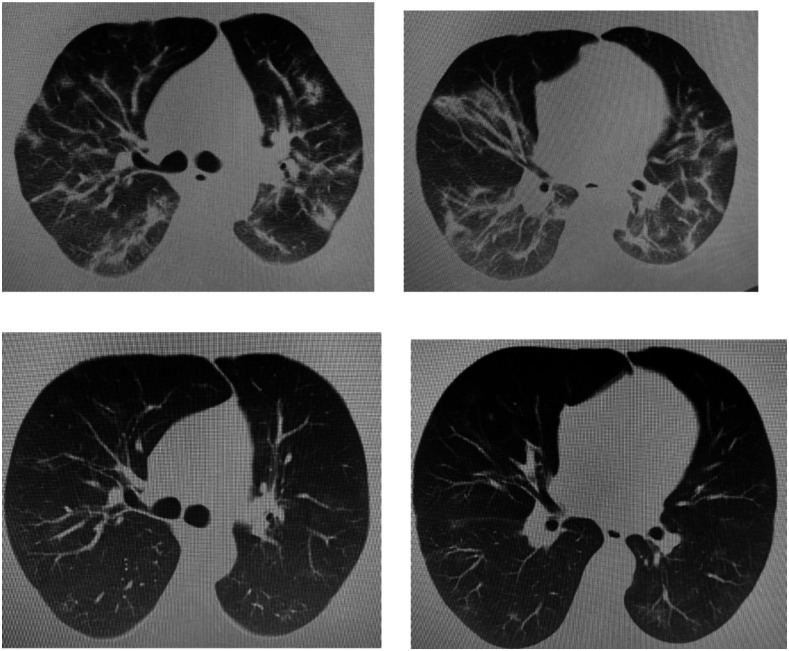

A 68-year-old man with a history of hypertension controlled with ramipril, hydrochlorothiazide, and amlodipine presented to the pulmonology department with persistent hiccups. The patient had a history of childhood poliomyelitis; he reported no alcohol intake and did not smoke. The patient disclosed that he had been hospitalized and treated with RT-PCR for positive COVID-19 pneumonia 15 days previously. At that time, he was treated with Favipiravir, Plaquenil, Ceftriaxone, and Enoxaparin, as recommended in the COVID-19 guidelines.10 During last 2 days of hospitalization he developed persistent hiccups and was discharged with metoclopramide. Chest CT scans are shown in Figure 2. The scans are from his first hospital admission.

Figure 2.

Computed tomographic chest scans of case 2 (top row) before and (bottom row) after coronavirus disease treatment.